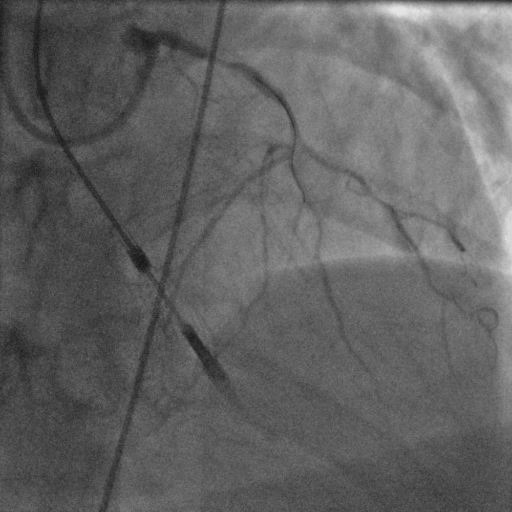

術(shù)中造影顯示左主干遠段原植入支架內(nèi)再狹窄85%。前降支近段狹窄80%,前降支中段完全閉塞。第一對角支開口狹窄99%,第二對角支中段狹窄50%。左回旋支細小,開口完全閉塞。右冠狀動脈近中段原植入支架內(nèi)通暢,遠段狹窄50%。

取EBU3.5指引導管至左冠口,在Expressman延伸導管及130cm APT微導管輔助下,采用Fielder XT-R導絲成功通過閉塞段送至前降支遠段。取2.0*20mm、2.5*20mm球囊于前降支近段-遠段病變處預擴張,前降支遠段-近段串聯(lián)植入2根支架。最后取2.0*20mm球囊于第一對角支開口病變處擴張。